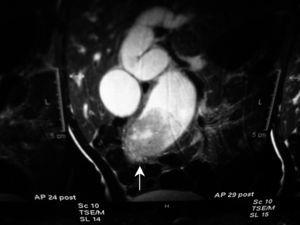

Se realiza una tomografía computarizada (TC) de abdomen que pone de manifiesto una dilatación de la vía biliar intrahepática, visualizándose una imagen redondeada de mayor densidad que la vesícula biliar que desplaza la arteria hepática (fig. 1). La colangiorresonancia realizada mostró una dilatación fusiforme del hepatocolédoco, visualizándose un defecto de repleción intraluminal en el colédoco distal, que ocasiona obstrucción y dilatación retrógrada de la vía biliar (fig. 2).

Figura 1.TC de abdomen: dilatación de la vía biliar intrahepática, visualizándose una imagen redondeada de mayor densidad que la vesícula biliar que desplaza la arteria hepática.